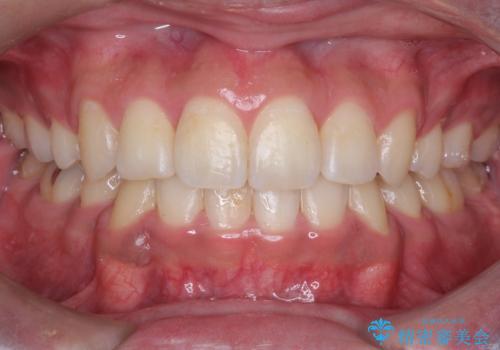

【前歯のがたつきでお悩みの方必見】インビザライン矯正の症例

担当医 奥村高広